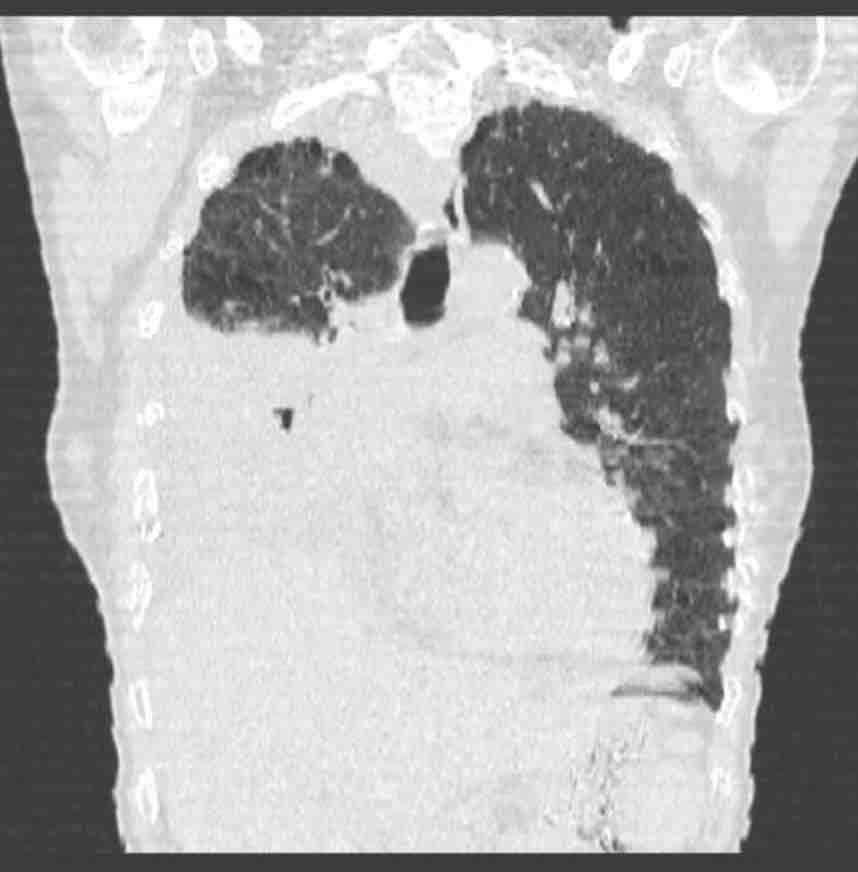

Sus problemas de salud comenzaron en abril de este año, con lo que se pensó que era una tos, para mayo ya era claro que el problema era mayor. Se le realizó en junio un TAC de Tórax que reveló un tumor y lo que ya parecía ser cáncer. Sin embargo, lo complicado de la zona evitó que al momento de obtener una prueba de tejido se pudiera diagnosticar correctamente con una biopsia, un segundo examen reveló la enfermedad.

Her health problems began in April of this year, with what was thought to be just a cough, by May it was already clear that the problem was greater. She underwent a chest CT scan in June that revealed a tumor and what already seemed to be cancer. However, the complexity of the area prevented her from being able to be correctly diagnosed with a biopsy at the time of obtaining a tissue test, a second examination revealed the disease.